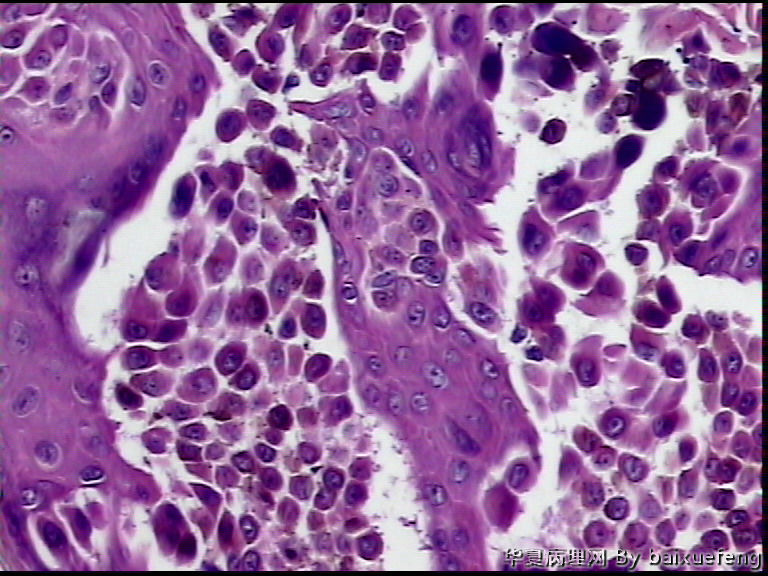

患者 女性 发现腰部皮肤肿物月余,表面0.5灰褐色结节

图3*100

图4*200

没异型性,考虑脂溢性角化

标记S-100,看看是不是个痣,如Spitz痣

也有可能是毛囊角化病或疣状角化不良瘤或棘层松解性的皮肤病变,图太少,不好确定

棘层松解性棘皮瘤?

考虑恶黑

考虑恶黑.图太少,不好确定

棘层松解性棘皮瘤

应该能排除恶黑吧,

恶黑我不考虑,

支持棘层松解性棘皮瘤。鉴别Spitz痣。